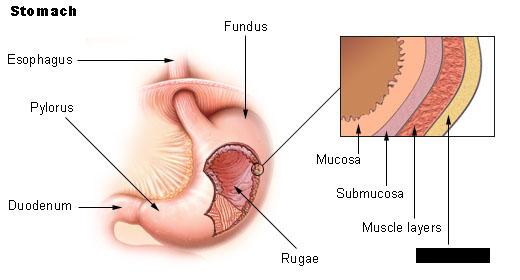

Body (of stomach)

Cardia (of stomach)

Duodenum

Fundus (of stomach)

Great omentum

Inner circular layer (of muscular externa)

Gastroesophageal sphincter

Mucosa

Outer longitudinal layer (of muscular externa)

Pyloric Sphincter

Pylorus (of stomach)

Rugae (of stomach)

Stomach

Submuscosa